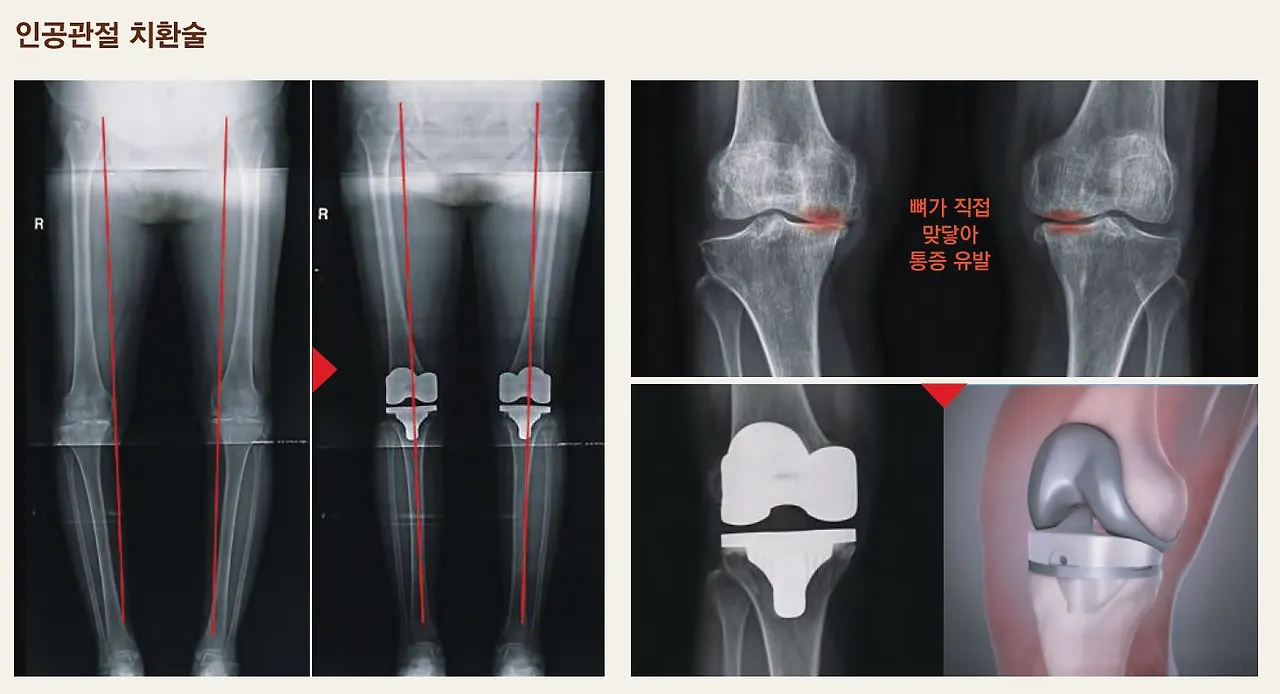

(3) 인공관절 치환술

인공관절 전치환술은 관절염이 심한 관절을 금속과 특수 플라스틱 등으로 바꾸어 주는 수술법으로 관절염이 심한해 아파서 걷기가 힘들거나 다리를 저는 경우, 조금만 걸어도 아프거나 겨우 계단을 오르내릴 수 있는 경우, 다리 모양이 비뚤어져서 걷기가 힘들거나, 관절이 굳어져서 불편한 경우 통증 없이 걷게 하기 위해 권장된다.

수술은 방사선 소견상 많이 진행된 관절염에만 시행하며, 이는 전문 의사의 판단에 따라 결정된다. 닳아진 관절표면을 인공관절로 치환하고 경골과 대퇴골 사이에 특수 플라스틱으로 만든 삽입물이 들어간다. 인공관절에는 수명이 있고 또한 수술 후 환자의 만족감 얻기 위해서는 적절한 환자에게 시행하는 것이 중요하다.

증상이 심하지 않은 사람은 방사선 사진에서 진행된 관절염이라도 수술을 받지 않는 것이 좋다. 또 너무 젊은 나이이거나, 심한 육체 노동 및 운동을 하고자 하는 사람들은 뼈에 붙여 놓은 인공관절이 분리되거나 쉽게 닳아 오래 쓰지 못하게 되므로 견딜 수만 있으면 하지 않는 것이 좋다.

감염이 있거나 수술할 부위에 염증이 있는 사람은 염증이 완전히 치유되고 난 다음에 수술을 해야 인공관절 수술 이후에 삽입물을 다시 빼내야 하는 상황을 막을 수 있다. 그 이외에도 병을 치료하고자 하는 의욕이 없거나 심한 정신 질환을 앓고 있는 분은 수술을 받지 않는 것이 좋으며, 척추(허리)에 이상이 있는 환자는 허리에서 신경이 눌려서도 무릎 통증이 발생하기에 수술을 신중히 고려해야 한다.